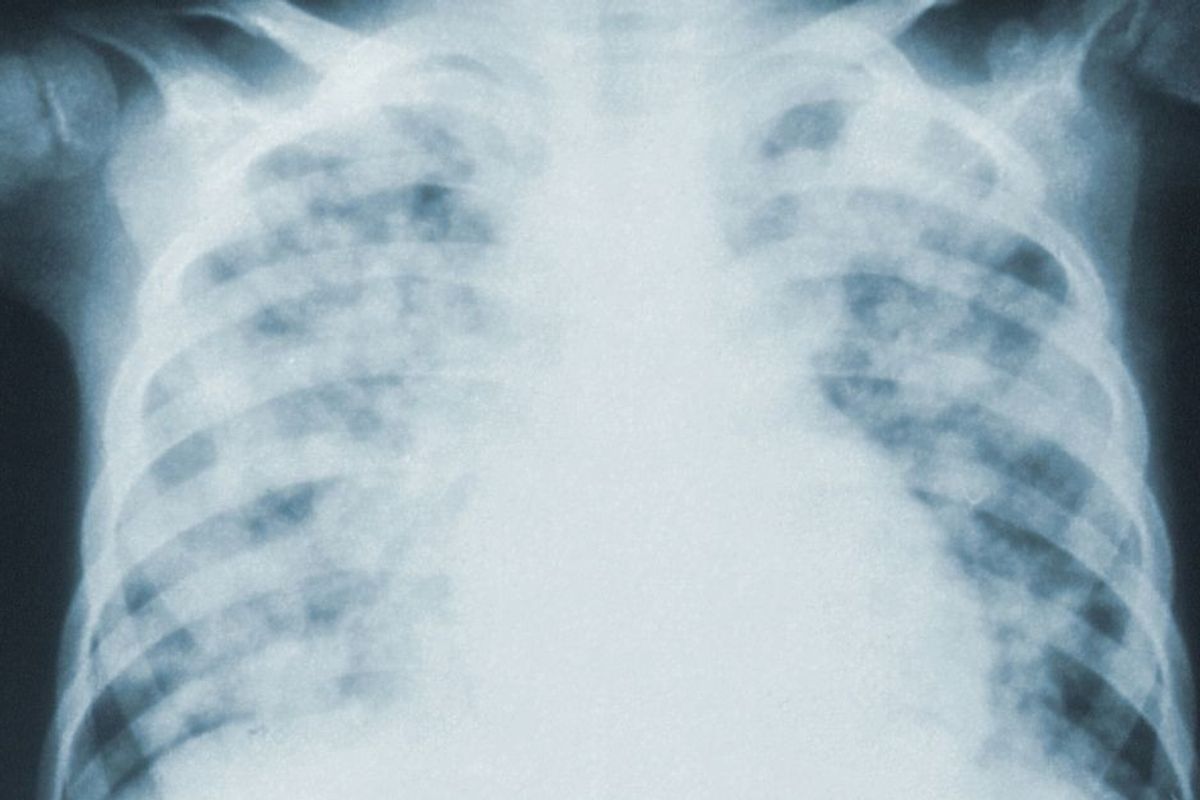

The death toll is harrowing enough. but what we don't hear about as much is what happens to the people who get sick with COVID-19 and don't die. Once a person's symptoms have begun improving and they test negative twice for the virus, they are considered "recovered." But that's not even close to the whole story for many who wage a weeks- or months-long battle with this illness.

"COVID 19 is the worst disease process I've ever worked with in my 8 years as an ICU nurse. When they say 'recovered' they don't tell you that that means you may need a lung transplant. Or that you may come back after d/c with a massive heart attack or stroke bc COVID makes your blood thick as hell. Or that you may have to be on oxygen for the rest of your life. COVID is designed to kill. It is a highly intelligent virus and it attacks everything. We will run out of resources if we don't continue to flatten the curve. I'm exhausted."

"I'm just getting over a "mild" case after over two months. There's scarring in my lower right lung and my stomach and digestion are a mess like never before. But I'm coughing way less and can take walks again.